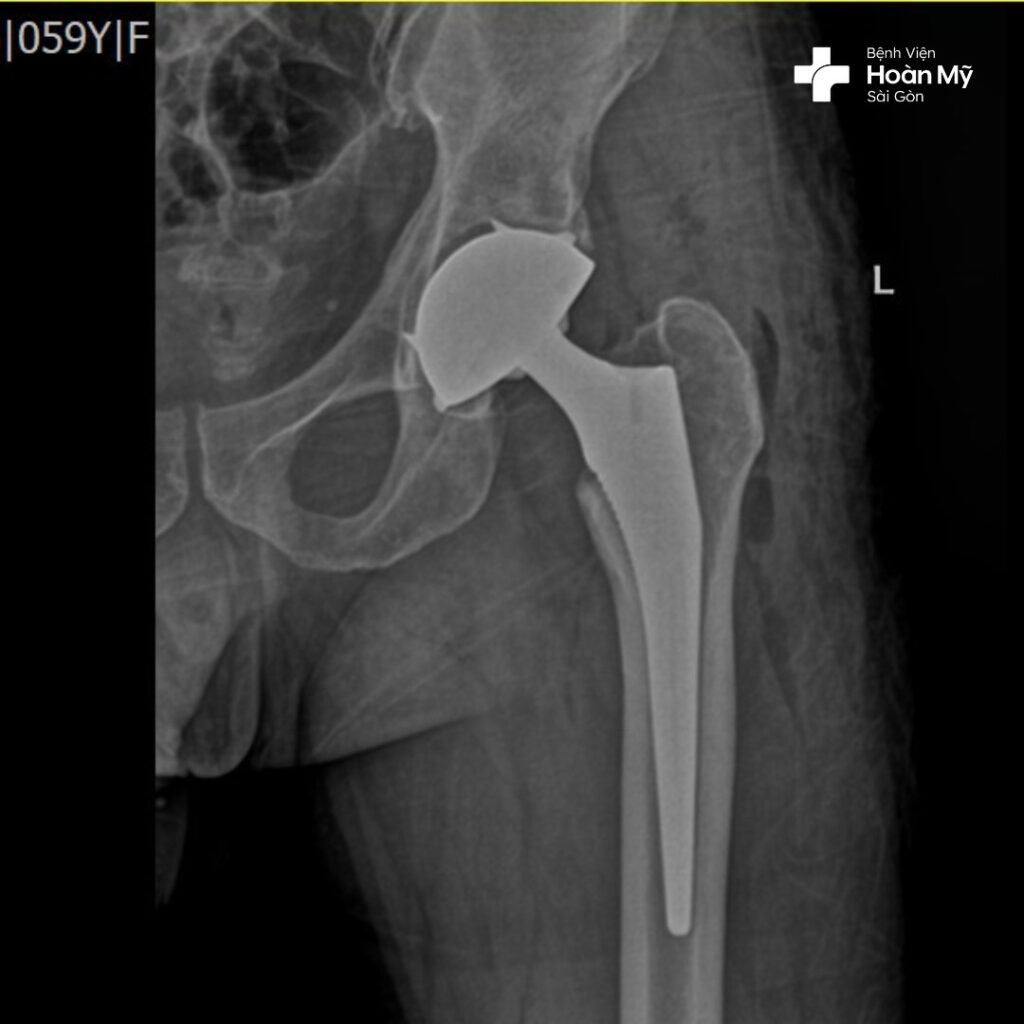

Hình ảnh X-quang sau phẫu thuật thay khớp háng của ông Đ.

Kỹ thuật thay khớp háng cùng lúc giúp ông Đ. giải quyết triệt để tình trạng hoại tử chỏm xương đùi với duy nhất một lần phẫu thuật. Điều này không những giúp tiết kiệm về mặt thời gian, khi người bệnh không phải đối mặt với hai lần phẫu thuật (thông thường lần phẫu thuật thứ hai phải cách lần phẫu thuật đầu tiên ít nhất 1-2 tháng), đồng thời tiết kiệm chi phí điều trị, giúp tâm lí người bệnh ổn định và lạc quan hơn.